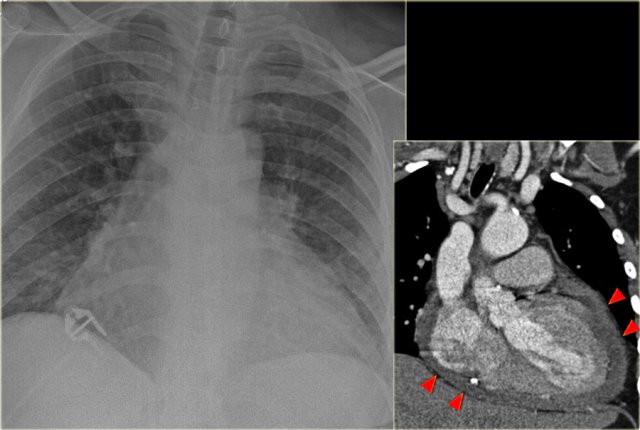

On the left a patient, who recently underwent a valve replacement.

There is a large cardiac silhouette, which could be the result of cardiomegaly.

Because of the recent cardiac surgery, the possibility of pericardial effusion was taken into account, which is nicely demonstrated on the CT-image.

On the left another patient with a large cardiac silhouette on the chest x-ray due to pericardial effusion.

Pericardial effusion is demonstrated on the coronal CT-reconstruction.